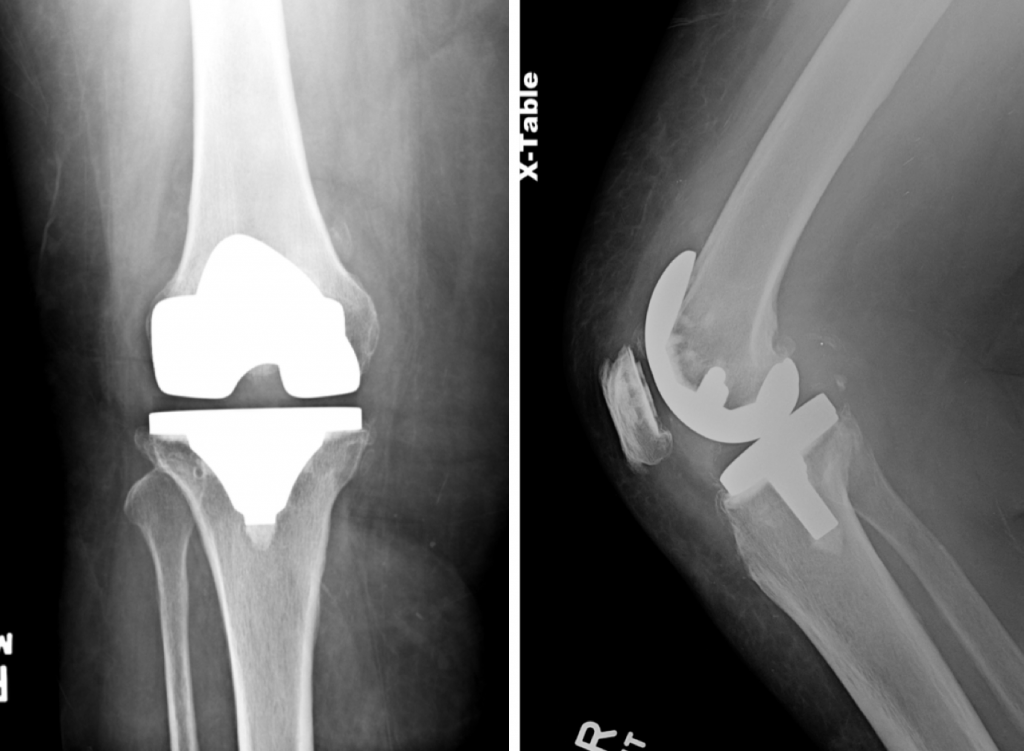

She underwent two stage exchange for infected TKA. During stage one, the prior knee implants were meticulously removed, and an articulated antibiotic spacer was placed using knee replacement implants, high dose antibiotic cement, and absorbable antibiotic beads. She was treated with IV antibiotics for 6 weeks. She underwent stage two reimplantation approximately three months later. The knee was reconstructed using a constrained condylar revision implant, hybrid/diaphyseal engaging stems, and a trabecular metal tibial cone.